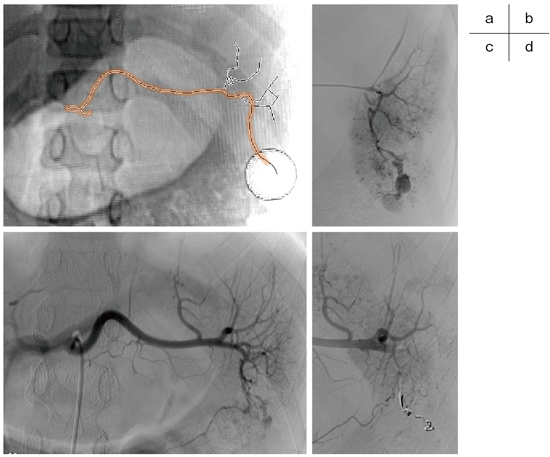

図4 小児の脾損傷症例

CTにて脾下極から腹腔内へ注ぐExtravasationを認め、直ちに血管撮影室へ移動。

血管造影の準備と同時進行で仮想透視画像を作成(a)。腹腔動脈の分岐位置と脾動脈・責任分枝の走行を把握。CT撮影から10分後の腹腔動脈撮影(b)。既に把握している責任分枝を迅速に選択し(c)、手技開始後9分で止血を確認した(d)。

仮想透視画像による血管分岐位置の把握は、多数の血管を選択しなければならない状況でより威力を発揮する。特に、転落外傷では複数の胸腰椎や肋骨の骨折による多発出血を伴うことがあり、腰動脈・肋間動脈を多数選択しなければならない場合がある。CT撮影から血管造影開始までの間に、10本以上の血管のパスをひとつひとつ描いている時間的猶予はないため、図5のように血管の起始部のみ点で示し、活動性出血の位置をマーキングしておく。画像診断班がそれを見ながら、術者の操作するカテーテル先端位置に対し、上下左右どの方向に動かせばいいか、目標血管は椎体のどの構造と重なっているかなどきめ細かく指示を出す。術者は透視画面だけを見てカテーテル操作に専念することができ、各血管を秒単位で選択することが可能となる。

図5 転落外傷による多発出血症例

高所からの墜落により骨盤骨折や傍椎体領域に多発出血を認めた。広範な組織挫滅に伴う凝固破綻をきたしており、ヒストアクリルにより多数の血管を塞栓した。